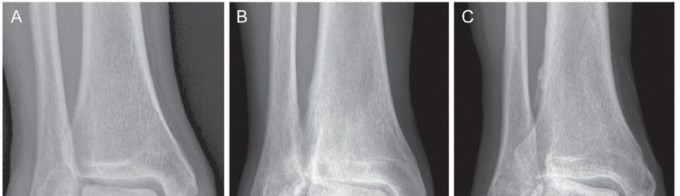

FIG 2 • Incompetence of the deltoid ligament. A. Distinct instability: AP weight-bearing radiograph shows a gapping of less than 5 degrees of the medial tibiotalar joint. B. Moderate instability: AP weight-bearing radiograph shows a gapping of 5 to 11 degrees of the medial tibiotalar joint. C. Severe instability: AP weight-bearing radiograph shows a gapping of more than 11 degrees of the medial tibiotalar joint.*

Chronic injury: Plain weight-bearing radiographs, including AP views of the foot and ankle (FIG 2), a lateral

view of the foot, and a hindfoot alignment view,13 should be obtained to rule out old bony avulsion fractures, secondary deformities of the foot (eg, valgus malalignment of the heel, dislocation at the talonavicular joint), and tibiotalar alignment (eg, medial gapping of the joint due to incompetence of the deltoid ligament).